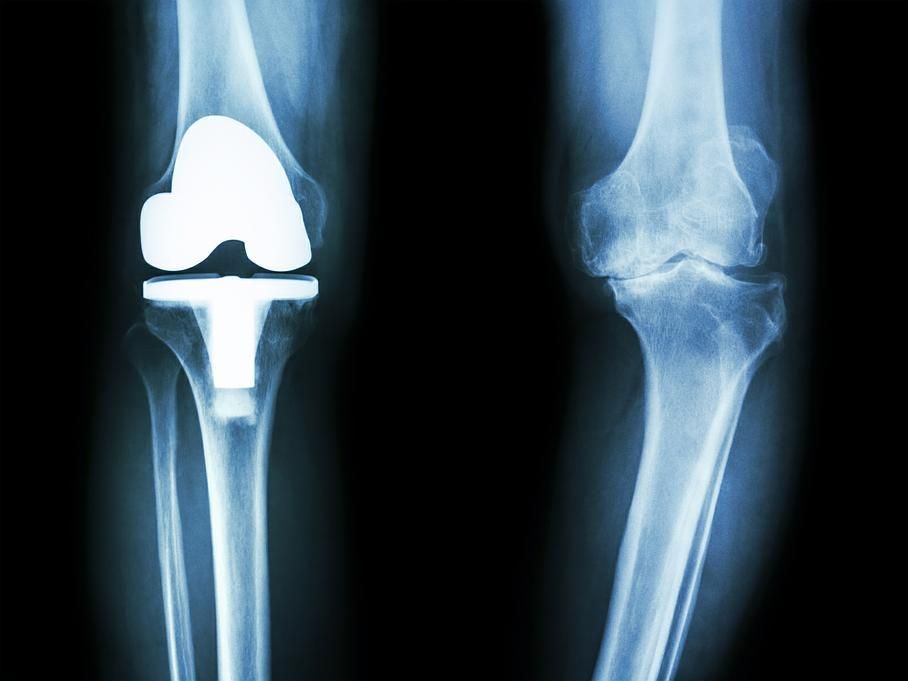

L’arthrose du genou ou gonarthrose:

L’évolution d’une arthrose du genou se fait par usure du cartilage et apparition de douleurs qui deviennent handicapantes pour la personne. Une fois le cartilage abîmé, il n’existe pas de solution médicale pour le reconstituer. Dès lors, un remplacement de l’articulation par une articulation artificielle, nommée prothèse, s’avère nécessaire.

Ceci se fait par une intervention chirurgicale, en préservant les muscles et les tendons. L’opération se fait quand les douleurs surviennent à la marche, et des fois la nuit, et qu’elles ne sont plus soulagées par aucun traitement médical. Il peut donc s’écouler plusieurs années entre la découverte de l’arthrose de la hanche et la mise place d’une prothèse.

L’intervention permet de rétablir une marche indolore et de reprendre certaines activités sportives. Le taux de satisfaction des patient(e)s est très élevé.